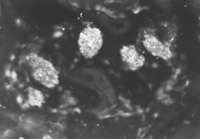

燒傷后7天(圖5-4-4),燒傷后14天(圖5-4-5),在該兩時間點鏡下可見比燒傷后4天繼續(xù)增多的表皮再生干細(xì)胞。潛在的再生干細(xì)胞即含人角蛋白19型細(xì)胞的數(shù)量達(dá)到燒傷療程中的峰值(數(shù)量最多)。至燒傷后21天(圖5-4-6)和28天(圖5-4-7)兩時間點潛在再生干細(xì)胞數(shù)量又減至一定的水平。觀察中發(fā)現(xiàn)患者經(jīng)濕性燒傷醫(yī)療技術(shù)治療后,潛在再生干細(xì)胞的增生狀態(tài)有一定的變化規(guī)律。潛在再生干細(xì)胞可能是表皮再生的干細(xì)胞的來源,這些在熒光顯微鏡下顯示熒光的細(xì)胞是深Ⅱ度和淺Ⅲ度燒傷后還存在的潛在的表皮再生干細(xì)胞。這些細(xì)胞可使燒傷濕性醫(yī)療技術(shù)治療的深Ⅱ度燒傷無瘢痕愈合,淺Ⅲ度燒傷皮膚再生。

圖5-4-4 經(jīng)MEBT/MEBO治療,燒傷后7天,角蛋白19型陽性細(xì)胞數(shù)量達(dá)峰值  ×200

圖5-4-5 經(jīng)MEBT/MEBO治療,燒傷后14天,角質(zhì)蛋白19型陽性細(xì)胞數(shù)量達(dá)峰值  ×200

圖5-4-1圖5-4-7均為應(yīng)用小鼠抗人角蛋白19型單克隆抗體于冰凍切片染色(生物素-抗生物素蛋白DSC體系間接免疫熒光)照片。